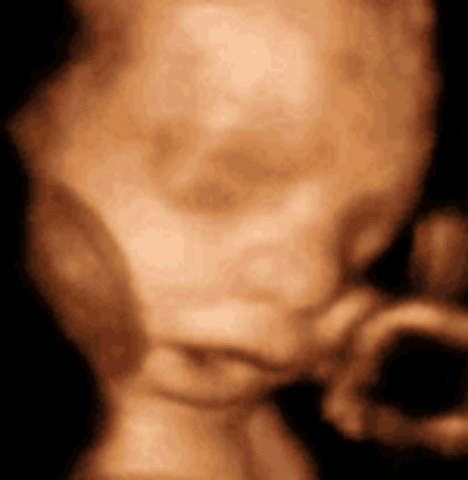

• Week Nineteen: Genitals recognizable

Week Nineteen: Genitals recognizable

the heartbeat can be captured on a ultrasound. you can tell wheither its a boy or girl.

• Week Twenty: The halfway point

Week Twenty: The halfway point

the baby can notice its moms voice. the hair start growing.